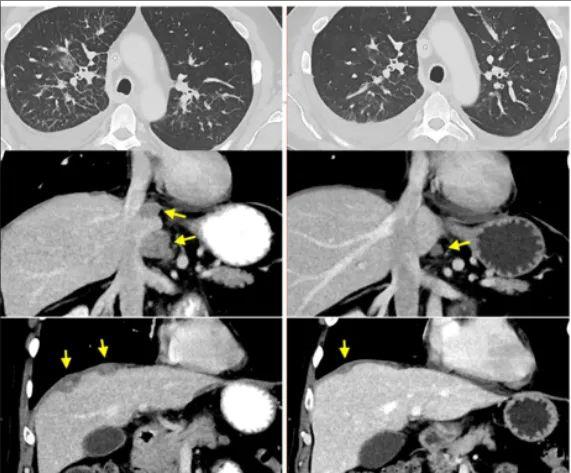

患者二

转移性结肠癌患者,支气管镜记录的右肺淋巴管炎受累(顶部,轴向)、腹膜后淋巴结和肝周肿瘤(中和底部,冠状方向)的消退。

患者三

转移性直肠癌患者的肝转移、门管淋巴结和多个肺转移的消退。